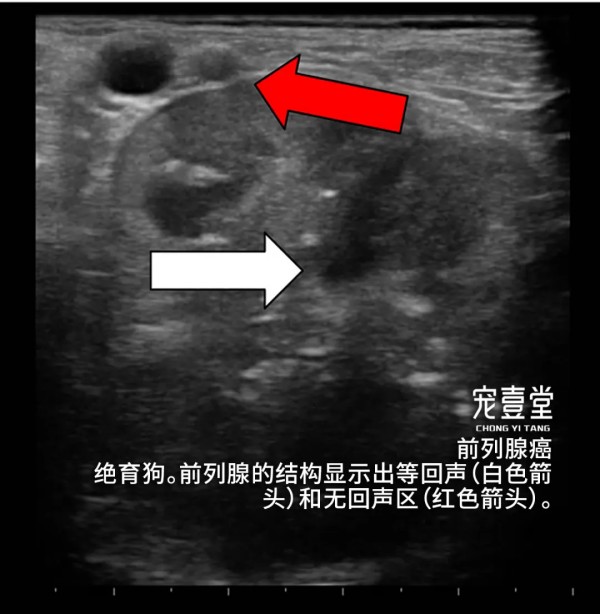

04【诊断标准】 1.根据临床症状、病史和体格检查做出初步诊断。触诊后腹部有明显疼痛反应,可摸到腹部肿块。 2.X线片可清晰看的见腹部前列腺位置的肿块。 3.超声检查可见前列腺明显增大并有强回声。当犬出现泌尿系统疾病时,除需检查肾脏、膀胱、前列腺外,睾丸及附睾也非常重要。前列腺的肿瘤有可能波及到或来自于睾丸及附睾的病变。 4.细针穿刺或活组织检查,可见肿瘤细胞。